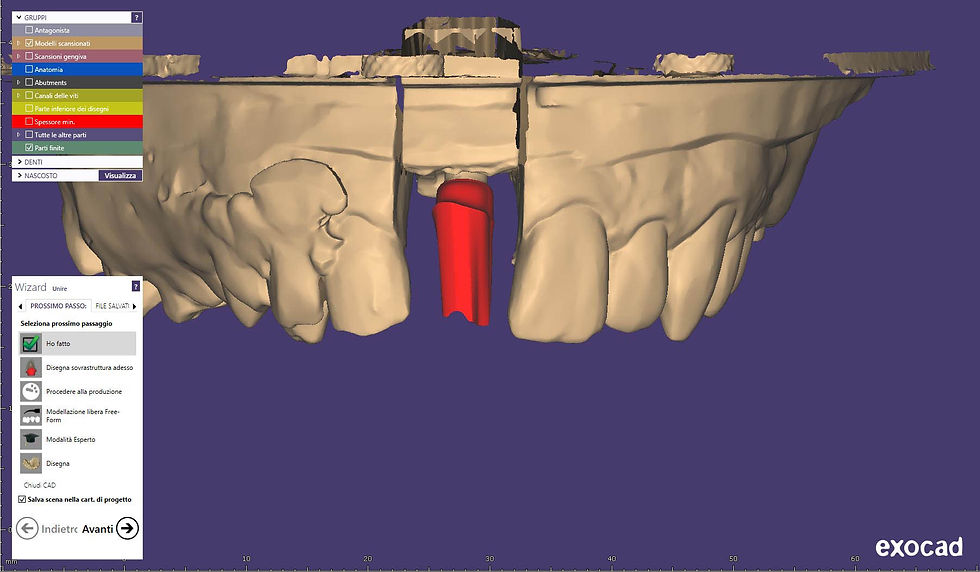

CAD-CAM design of the definitive crown.